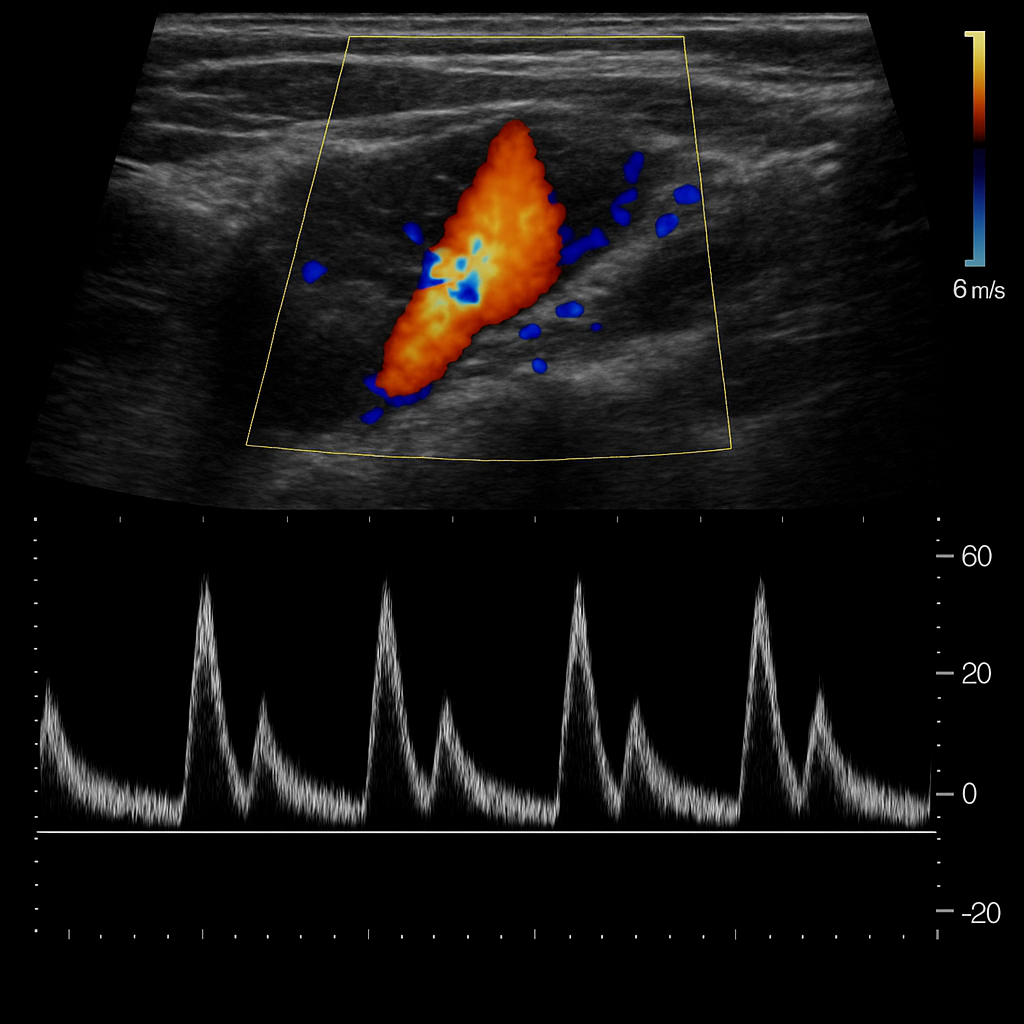

Durante el tercer trimestre del embarazo, la ecografía Doppler se convierte en una

herramienta fundamental para evaluar cómo está el bebé dentro del útero. Este examen

permite observar el flujo sanguíneo entre la madre, la placenta y el feto, asegurando

que el oxígeno y los nutrientes lleguen correctamente, lo que es clave para un desarrollo

saludable antes del parto.

La ecografía Doppler mide la velocidad y dirección del flujo sanguíneo en arterias y

venas específicas del bebé, la placenta y el útero. Con estos datos, el equipo médico

puede identificar de forma temprana si existe alguna alteración en la circulación, lo que

podría alertar sobre: